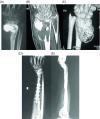

Giant cell tumor (GCT) of bone is a locally aggressive benign neoplasm that is associated with a large biological spectrum ranging from latent benign to highly recurrent and occasionally metastatic malignant bone tumor. It accounts for 4-10% of all bone tumors and typically affects the meta-epiphyseal region of long bones of young adults. The most common site involved is the distal femur, followed by the distal radius, sacrum, and proximal humerus. Clinical symptoms are nonspecific and may include local pain, swelling, and limited range of motion of the adjacent joint. Radiographs and contrast-enhanced magnetic resonance imaging (MRI) are the imaging modalities of choice for diagnosis. Surgical treatment with curettage is the optimal treatment for local tumor control. A favorable clinical outcome is expected when the tumor is excised to tumor-free margins, however, for periarticular lesions this is usually accompanied with a suboptimal functional outcome. Local adjuvants have been used for improved curettage, in addition to systematic agents such as denosumab, bisphosphonates, or interferon alpha. This article aims to discuss the clinicopathological features, diagnosis, and treatments for GCT of bone.